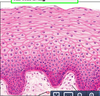

Stratified Squamous